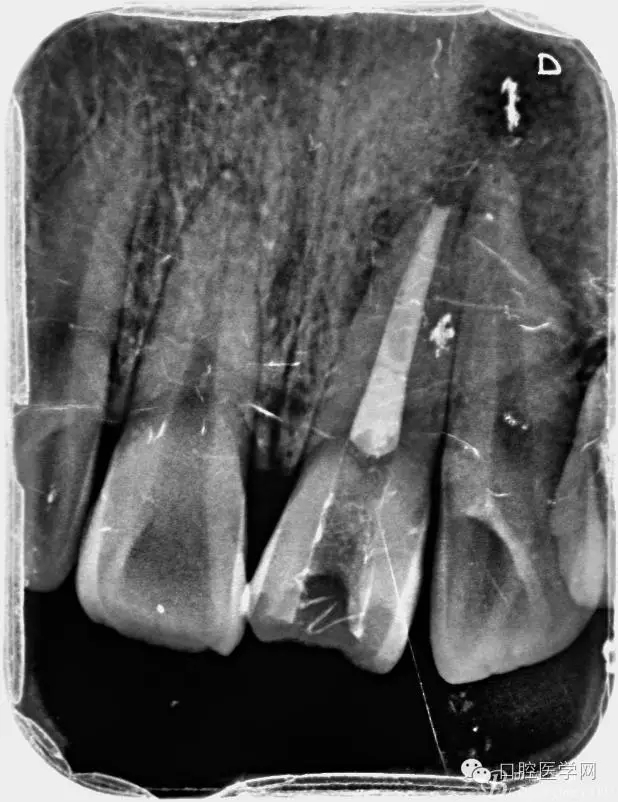

2、根管填充的界限

根管的解剖界限是从髓室根管入口到根尖部牙本质- 牙骨质交界处(生理性根尖孔) 。理想的根管充填应该是对生理性根尖孔冠方以上进行严密的三维封闭。临床上根据X线牙片判断根管充填的质量。牙片上充填材料与根管壁紧密接触一般被认为充填严密。关于充填止点,由于牙本质- 牙骨质界离根尖孔外表面平均距离为0. 5~0. 7 mm,同时相当多的根尖开口并不位于X线片的根尖处。因此临床上认为材料充填至距X线片牙根最尖端0. 5~1 mm (也有认为0. 5~2mm)为适填。

5、根管充填的技术方法

为达到更为理想的根充效果,研究人员和牙髓病医生一直在探索根管充填技术,并且发展出多种可供选择的方法。Ingle]将其归纳为3 类: ①“牙胶尖+封闭剂”式; ②“根尖1 /3充填”式; ③“注射或螺旋充填”式。目前临床广泛采用的主要是“牙胶尖+封闭剂”方式。按照充填压力的方向(侧向或垂直)不同和牙胶温度(冷或热)不同,根管充填有2 种基本技术:冷牙胶侧方加压充填和热牙胶垂直加压充填。现有的各种充填方法均是这2 种基本方法基础上的发展或改良。医生可根据方法的优缺点以及个人习惯选择使用。